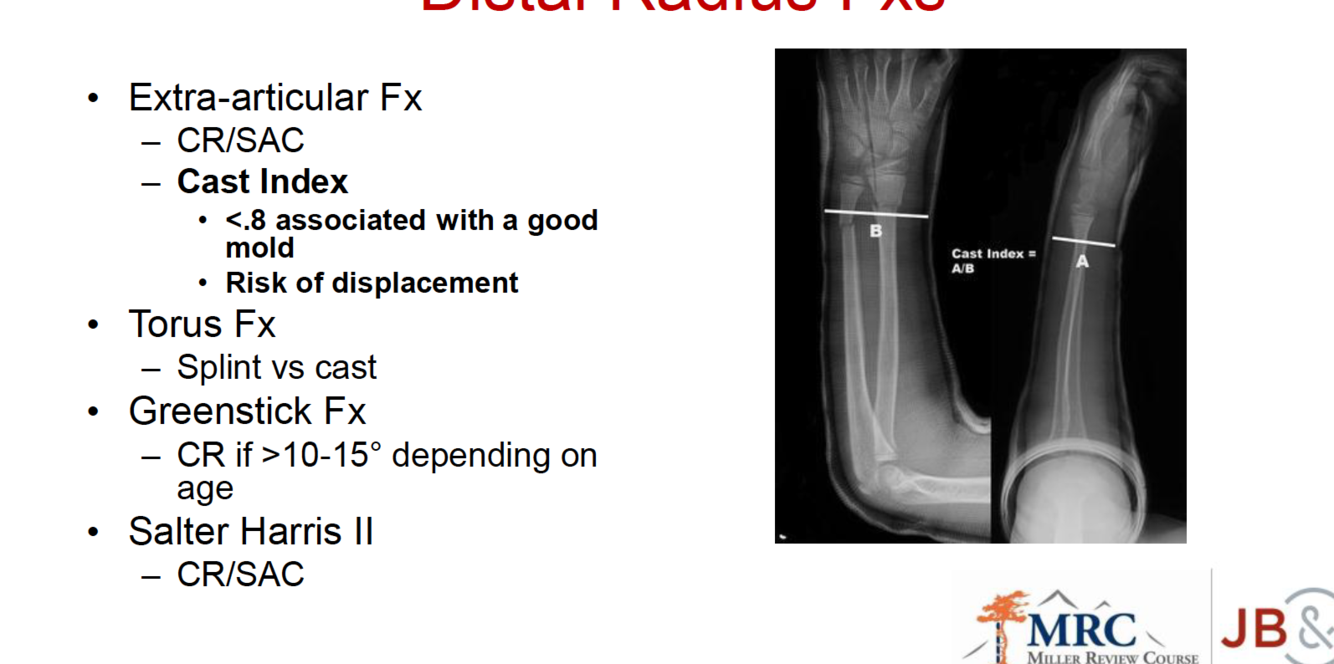

What is a good cast index and what is it related to?